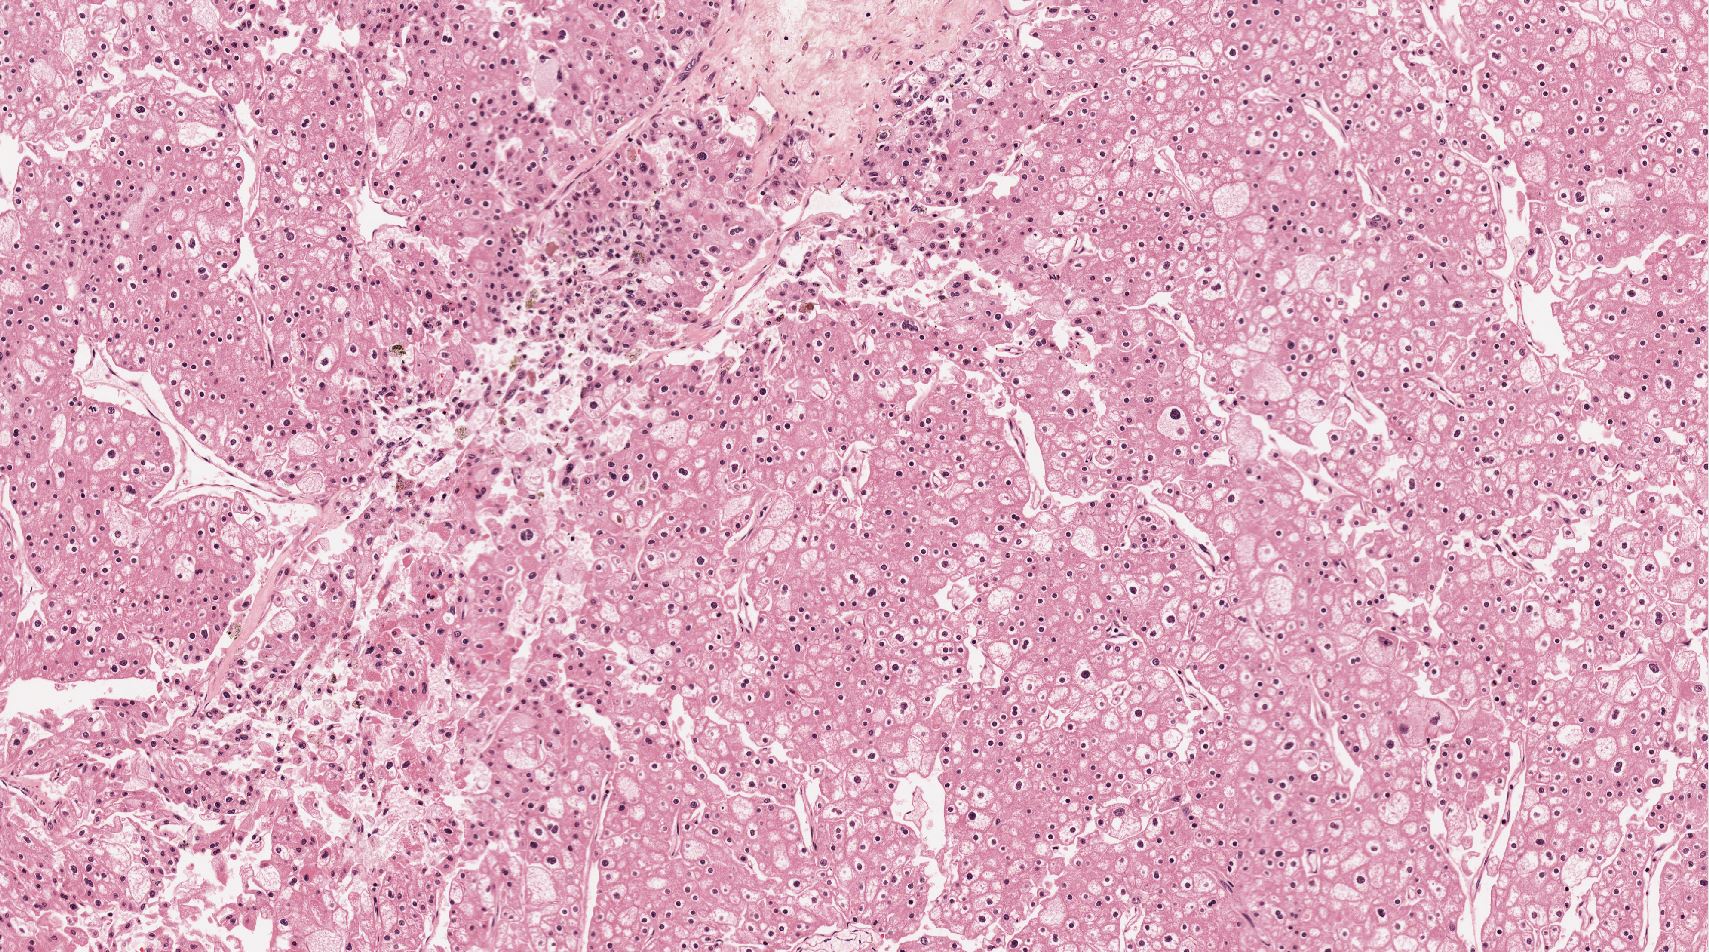

Renal tumor grading

Case ID: 544